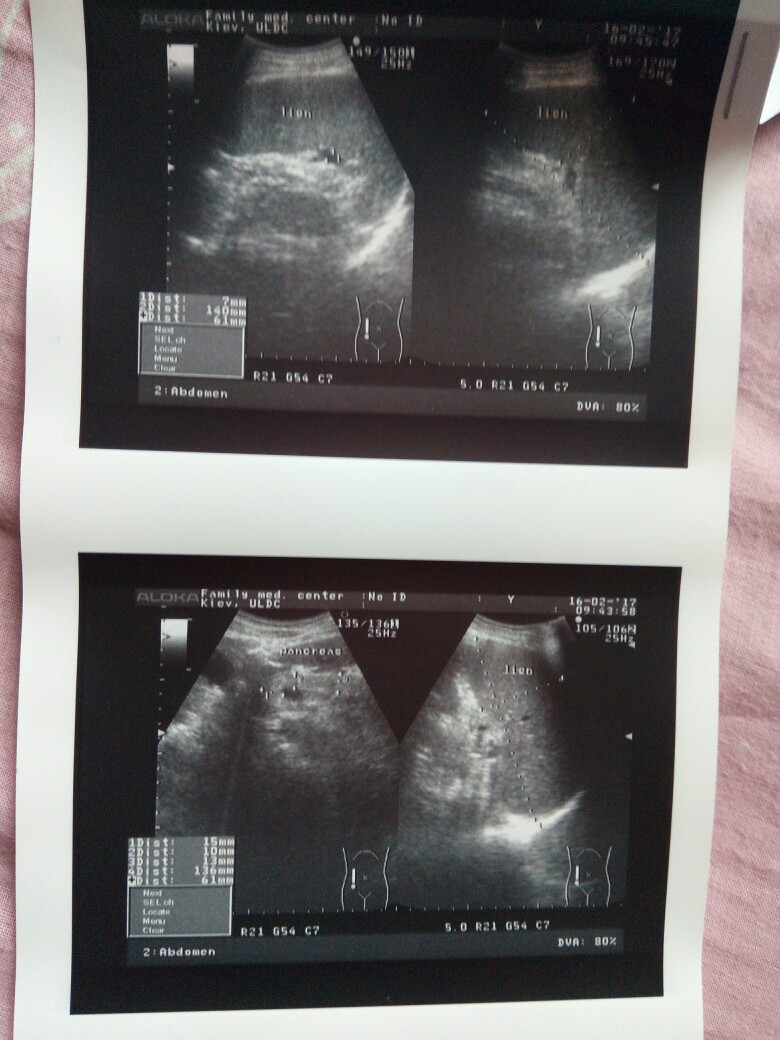

Сегодня забрала опись узи, сплошная печаль

Вложения

IMG_20170223_133333-780x1040.jpg

IMG_20170223_132125-780x1040.jpg

IMG_20170223_132050-602x640.jpg